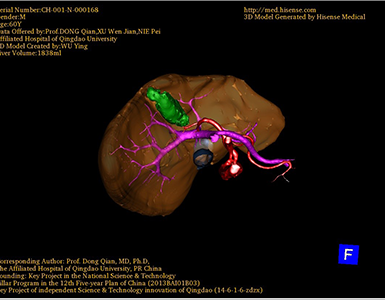

将0.625mm双源薄层CT资料的静脉期和动脉期Dicom格式文件导入海信CAS系统。

通过调节窗宽窗位调整CT序号,对肿瘤,肝实质,胆囊,下腔静脉,肿瘤,肝动脉、门静脉及肝静脉等进行三维重建;系统自动计算肿瘤体积和肝脏体积。

术前手术方案的规划。

术前三维重建:

重建图片